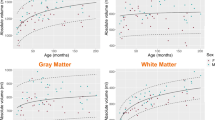

The T1 relaxation times of the pediatric brain rapidly decrease in all regions within the first 3 years of age, followed by a significantly slower reduction until adulthood (Fig. 2). This age-dependent course of T1 values can be described by an exponentiation function axr + b with fractional (negative) power r = −n/10. The steepest decline was observed for the frontal and occipital white matter. Especially in the first 6 months of age, the T1 relaxation times varied substantially. The R2 after hyperbolic transformation ranged from 0.84 to 0.94 (P<0.001 for each region). Differences in T1 values between individual structures were all highly significant (P<0.01). Bland–Altman plots for inter-rater variability are shown in Online Supplementary Resource 1. Both intra-rater reliability and inter-rater variability were in most cases excellent (intraclass correlation coefficient [ICC] > 0.92). The inter-rater reliability in bulbus oculi was good (ICC 0.78).

T1 relaxation times in different brain regions of children with inconspicuous cranial MRI as a function of age. a Frontal white matter. b Occipital white matter. c Putamen. d Globus pallidus. e Caudate nucleus. f Thalamus. g Brainstem. h Dentate nucleus. All regions reveal a steep decrease of T1 values with age, with an exponential characteristic. i For comparison, the age-independent water proton T1 relaxation times of bulbus oculi is also demonstrated. Solid lines represent the regression function of the mean. Dashed lines indicate the 95% confidence interval

We found a very rapid decrease in T1 relaxation times in each region of the brain within the first 2 years of age, which turned into a slight linear decrease from about 5 years of age until adulthood. The initial drop was most pronounced in white matter and can be explained by its dynamic maturation, especially from myelination. In contrast to the literature, our data suggest that the initial steep and late flat drop can be described more closely by a reciprocal exponential function than by a logarithmic function. Deoni et al. [16] analyzed the degree of myelination, more precisely the myelin water fraction, in the white matter of 153 infants and toddlers ages 3–60 months. Their T1 determinations relied on the mcDESPOT technique, which represents FLASH acquisitions with variable flip angles, which are known to have inconsistent slice profiles. Moreover, a comparison with the present data is precluded because no direct T1 values have been reported. Eminian et al. [18] measured T1 relaxation times of gray and white matter in 42 children ages 1–20 years using MP2RAGE. Four regions matched those in our study: the nucleus caudatus, putamen, thalamus and frontal white matter. Compared to our results, the T1 relaxation times recorded by Eminian seem similar but slightly higher on average (pooled data of children of 5 years and older: putamen 1,172 ms versus 1,162 ms, nucleus caudatus 1,297 versus 1,272 ms, thalamus 1,081 ms versus 1,101 ms, frontal white matter 806 versus 758 ms and more dispersed. Recently Lee et al. [29] presented normal values for T1 and T2 relaxation as well as proton density in a pediatric cohort of 89 children with a median age of 18 months with a synthetic MRI sequence. Concordant to our results, this study again demonstrated the very rapid drop in T1 relaxation time in the first years followed by a much slower decline until adulthood. Between Lee’s and our study, three regions of interest overlapped. The authors split their cohort into different age groups. The T1 relaxation times in the age group with the least decrease (i.e. older than 5 years) were on average slightly lower than the results in our study: in the frontal white matter 707 ms versus 758 ms, in the thalamus 951 ms versus 1,101 ms, and in the nucleus caudatus 1,160 versus 1,272 ms. While deviations for older children probably reflect systematic technical differences as previously suggested [4], differences in the lower age range might additionally be caused by the comparatively low number of cases. In our work, separate evaluations for boys and girls were omitted because of the expected minimal differences and the significantly higher number of cases otherwise needed.